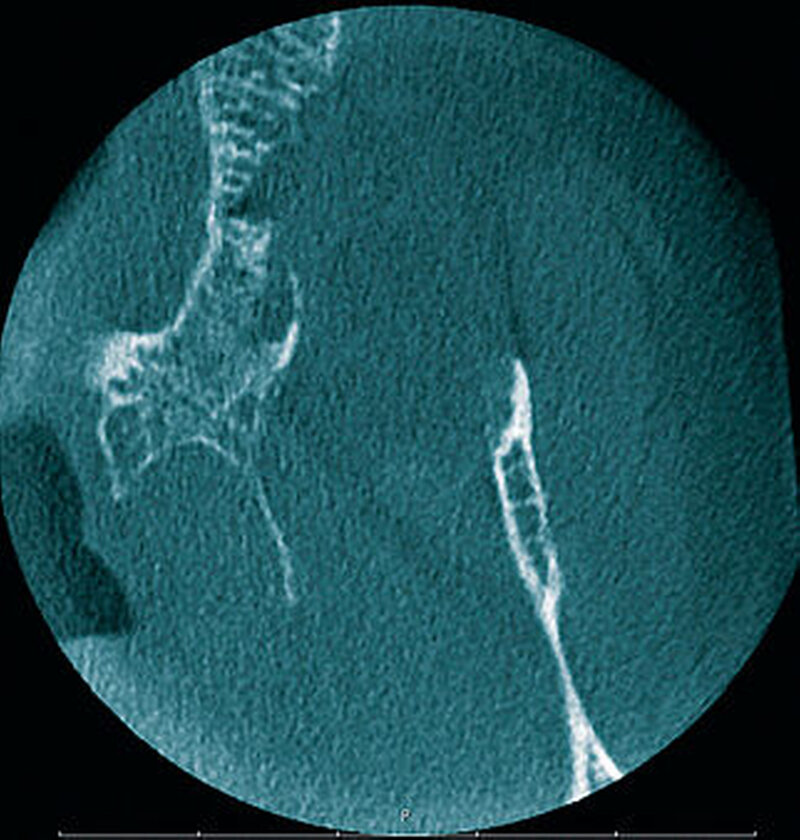

In der alio loco angefertigten Panoramaschichtaufnahme (Abbildung 2) stellte sich in regio 27 ein an eine Extraktionsalveole erinnernder Knochendefekt dar. Die Patientin konnte sich aber nicht mehr erinnern, wann sie den Zahn verloren hatte. Nebenbefundlich zeigte sich neben einem parodontal geschädigten Restgebiss ein apikal beherdeter Zahn 36. Eine Therapie lehnte die Patientin allerdings ab.

In der digitalen Volumentomografie fiel ein osteolytischer Prozess in der Oberkiefermolarenregion links auf, wobei die bukkale Kompakta weitstreckig unterbrochen war bei noch intakter lateraler und basaler Kieferhöhlenbegrenzung. In einzelnen Schichten tunnelierten die osteolytischen Bereiche die Kompakta (Abbildung 3).

Radiologisch stellen sich braune Tumore als Osteolysen dar, wobei der Knochen bei entsprechender Größe des Befunds auftreiben kann. Häufig zu erkennen ist eine Auflockerung und Rarefizierung der Spongiosa. Die Kompakta kann ausgedünnt sein beziehungsweise völlig fehlen, wobei es häufig zu Tunnelierungen kommt. Das bedeutet, dass die Spongiosa radiologisch stärker affektiert erscheint als die darüber befindliche Kompakta [Freyschmidt, Ostertag et al., 2010].